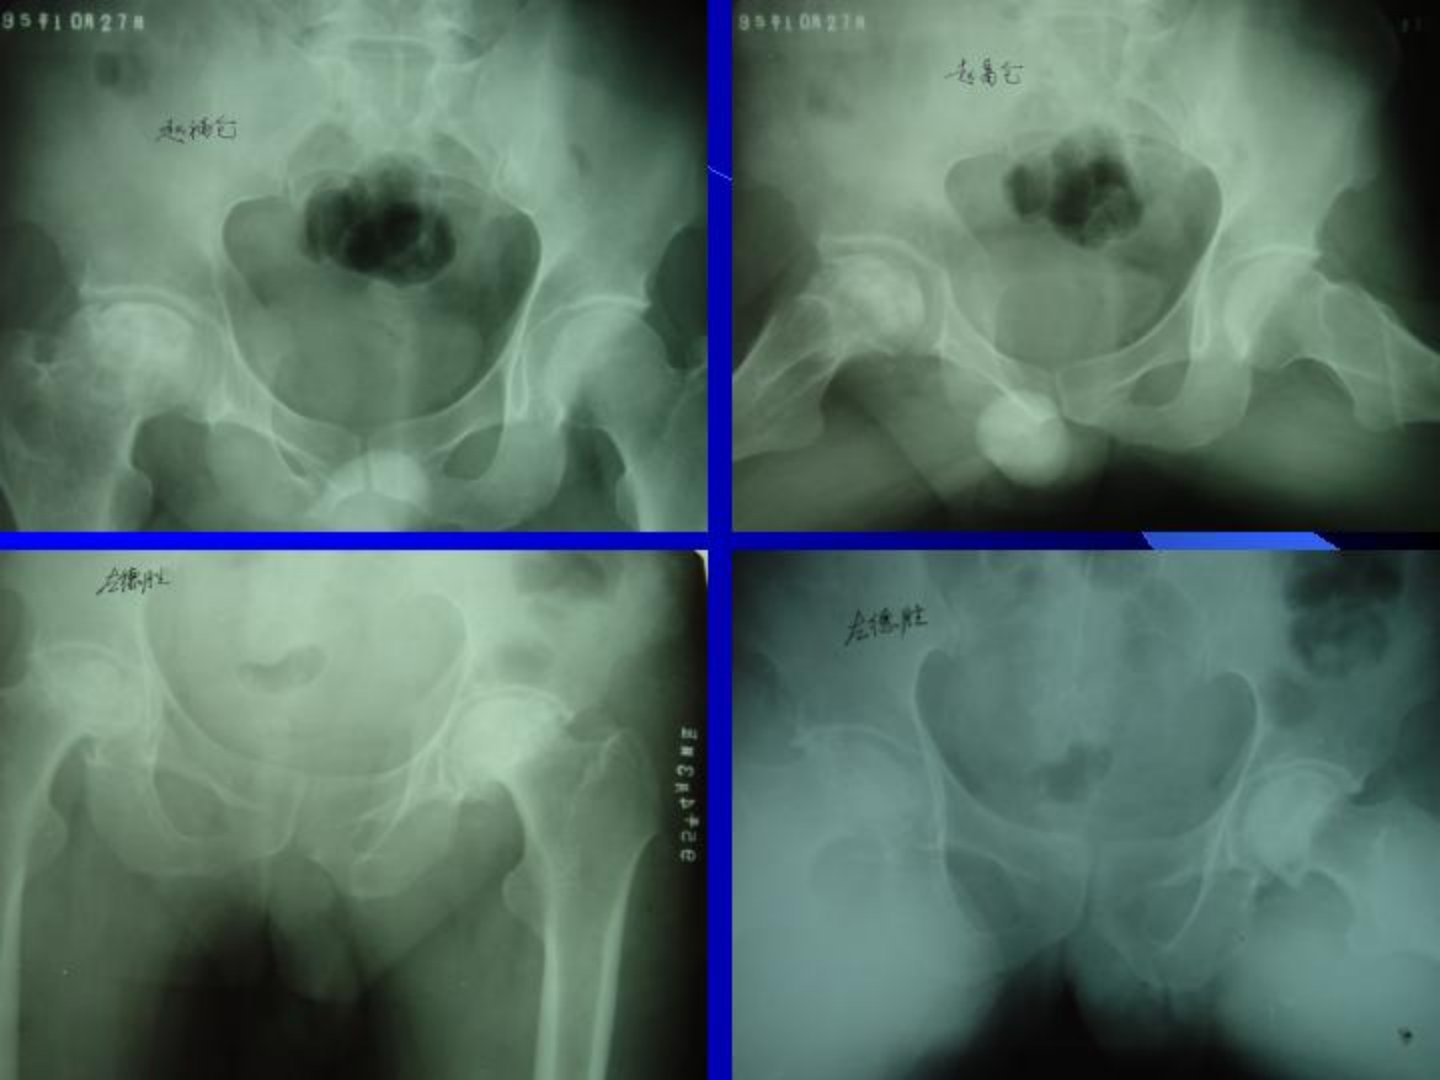

成人股骨头坏死的诊治摘要成人股骨头缺血性坏死(ANFH)是骨科常见病由多种因素导致股骨头血液供应破坏引发骨细胞等坏死。病因多样分创伤性(如股骨颈骨折等髋部创伤)、非创伤性(激素、酒精中毒最常见酒精性已居首位还有其他多种病因)和特发性三大类。临床表现上多为双侧发病有激素使用或长期酗酒史主要症状是髋部疼痛早期有压痛、4字试验阳性X线有特定表现后期症状加重、活动受限。诊断依赖病史、症状、体征及多种检查其中MRI是早期诊断最先进方法股骨头核心活检结果最为准确。临床分期对决定治疗方案很关键以往方法多样1997年世界骨循环研究学会设立国际骨坏死分期标准。治疗是难题非手术治疗包括停止使用激素、戒酒等一般治疗及对症处理。手术治疗方面髓芯减压术适用于部分期别;股骨转子间区截骨术适用于部分患者;带肌蒂或血管蒂骨瓣移植术适用于特定期别早期;人工关节置换术中股骨头表面置换术有适用人群但有缺点人工股骨头置换术因诸多缺点现已少用人工髋关节置换术是晚期有效治疗方法不同固定方式适用于不同年龄患者。